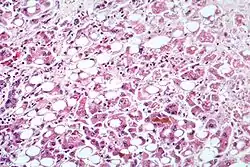

يمكن تشخيص الإصابة بـالتهاب الكبد الفيروسي (ج) بعمل تحليل مخبري للدم، يكشف فيه عن وجود الأجسام المضادة للفيروس. كما أن تحليل وظائف الكبد في الدم يبين مدى تأثر خلايا الكبد بـ الالتهاب الكبدي الفيروسي ج. يلجأ الطبيب في الحالات المتقدمة لأخذ عينة من الكبد لمعرفة حالة خلايا الكبد وتأثرها بوجود الالتهاب الكبدي الفيروسي –ج.